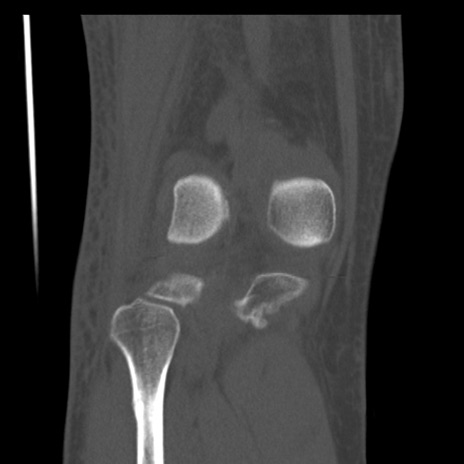

右膝関節CT

横断像